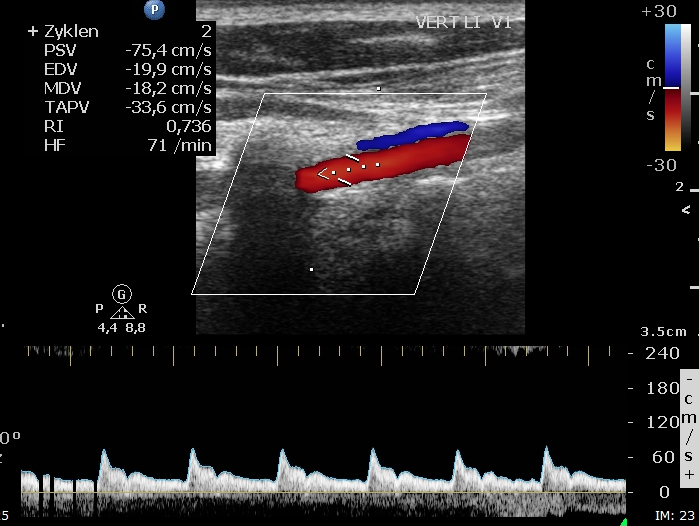

Vorerst finden Sie unkommentiere Bilder ... weitere Informationen folgen.